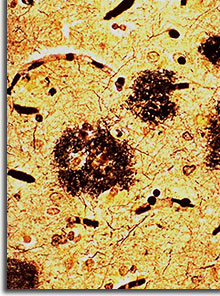

Nouveauté cette année, l’organisation d’ateliers cliniques et de discussions sur les principales difficultés diagnostiques et de prise en charge posées par les syndromes démentiels. Agir sur la plaque amyloide pour éviter sa formation ou accélérer son élimination constitue l’objectif n°1 de la majorité des stratégies thérapeutiques médicamenteuses dans la maladie d’Alzheimer.